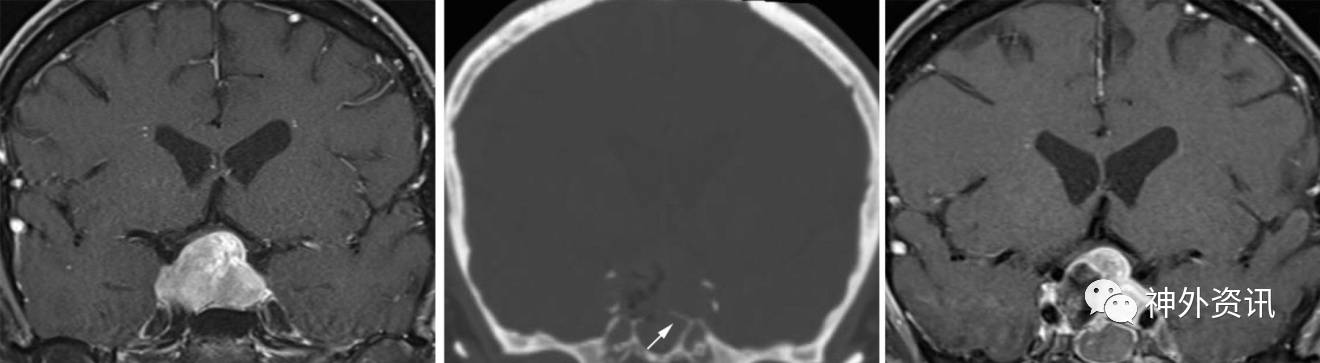

图20. 伴症状性视交叉压迫的复发垂体瘤一例(左图)。术后影像显示鞍底骨质部分移除(中图,箭头),导致肿瘤切除不全(右图)。该患者接受了再次手术,扩大鞍底骨窗,充分切除肿瘤。